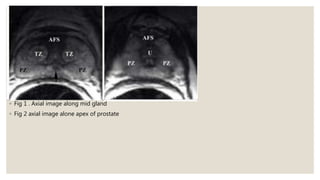

◦ Fig 1 . Axial image along mid gland

◦ Fig 2 axial image alone apex of prostate

• #15 Fig 1. T2 Coronal image of the prostate illustrates the central zone (CZ) and peripheral zone (PZ). Note that CZ has the shape of an inverted cone with its base oriented towards the base of the gland and is homogeneously hypointense as it contains more stroma than glandular tissue. CZ is well seen in younger patients; however age-related expansion of the transition zone by benign prostatic hyperplasia (BPH) may result in compression and displacement of the CZ leading to its poor visibility. FIG. 2 aAxial image of the prostate base, that constitutes the upper 1/3 of the gland just below the urinary bladder, shows the following anatomical zones: anterior fibromuscular stroma (AFS) containing smooth muscle, which mixes with muscle fibers around the urethra (U) at the bladder neck and contains no glandular tissue, hence it is markedly hypointense; central zone (CZ) surrounding the ejaculatory ducts (arrows); and peripheral zone (PZ) that covers the outer lateral and posterior regions of the prostate.

• #16 Fig 1 .Axial image of the midgland, that constitutes the middle 1/3 of the prostate and includes verumontanum in the mid prostatic urethra, shows anterior fibromuscular stroma (AFS) and transition zone (TZ) tissue around the urethra. Note increasing volume of peripheral zone (PZ) in the midgland where it occupies the outer lateral and posterior regions of the prostate and is homogeneously hyperintense. Arrow points to converging ejaculatory ducts as they enter the mid prostatic urethra at verumontanum. Fig 2 Axial image of the apex of the prostate, that constitutes the lower 1/3 of the prostate, shows hypointense anterior fibromuscular stroma (AFS) in front of the urethra (U). Peripheral zone (PZ) makes up most of the apex of the prostate.